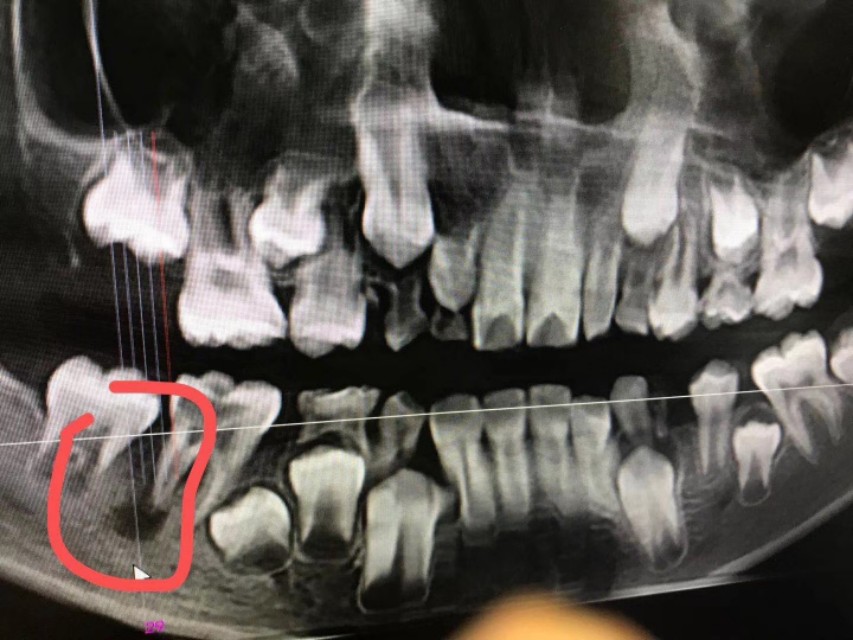

患儿,男性儿童,半年前出现右侧颌面反复流脓,家属半年碾转就诊于数家医院的耳鼻咽喉科和口腔科,多次切开排脓不愈,最后一次在我老师所在科室行全麻瘘管局部清扫手术,自认为手术彻底,谁知10余天后就复发,百思不得其解,复诊时口腔检查,终于发现右下一牙轻微叩痛,(患儿未诉牙自发症状),嘱其再返口腔科就诊,拔除患牙,右颌下瘘管随之而愈,虽然患儿最终得以痊愈,但是过程曲折受尽折磨,患儿的主刀医生已经是头颈外科的顶级专家,依然难免会有差错的时候,行医之路,如履薄冰,特以同道分享!

2、术中未见瘘管,均为肉芽,术后病理亦未报瘘管,只报炎症,未起疑心

3、术中并未见下颌骨皮质受损(是否舌侧可能),排除了牙源性可能